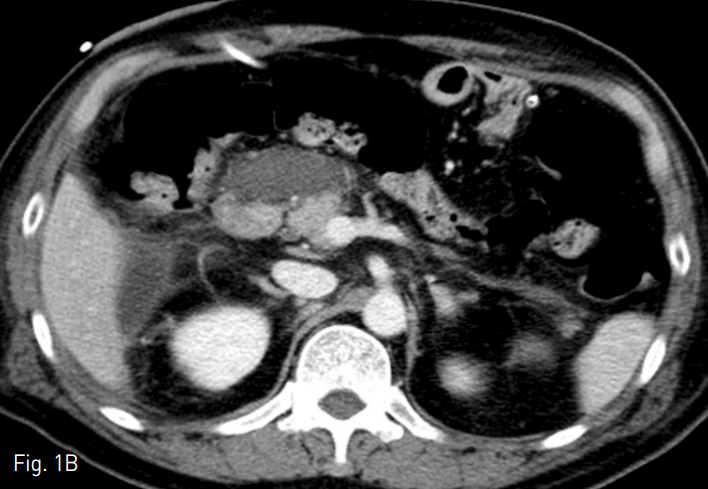

시술 1일 뒤 시행한 경과 관찰 전산화단층촬영에서 이전에 보이던 문합부위 주변과 십이지장 절단 끝에 액체저류는 보이지 않았음 (Fig. 7). 그 외 동맥류 등의 수술의 합병증 없이 퇴원하고 외래로 항암치료 계획함.

Fig. 7

Contrast-enhanced axial CT scans on 1 week after the procedure show markedly decreased extent of fluid collection with PCD catheter insertion.